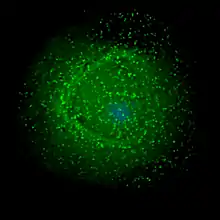

HIV assembling on the surface of an infected macrophage. The HIV virions have been marked with a green fluorescent tag and then viewed under a fluorescent microscope.

The final step of the viral cycle, assembly of new HIV-1 virions, begins at the plasma membrane of the host cell. The Env polyprotein (gp160) goes through the endoplasmic reticulum and is transported to the Golgi apparatus where it is cleaved by furin resulting in the two HIV envelope glycoproteins, gp41 and gp120.[87] These are transported to the plasma membrane of the host cell where gp41 anchors gp120 to the membrane of the infected cell. The Gag (p55) and Gag-Pol (p160) polyproteins also associate with the inner surface of the plasma membrane along with the HIV genomic RNA as the forming virion begins to bud from the host cell. The budded virion is still immature as the gag polyproteins still need to be cleaved into the actual matrix, capsid and nucleocapsid proteins. This cleavage is mediated by the packaged viral protease and can be inhibited by antiretroviral drugs of the protease inhibitor class. The various structural components then assemble to produce a mature HIV virion.[88] Only mature virions are then able to infect another cell.